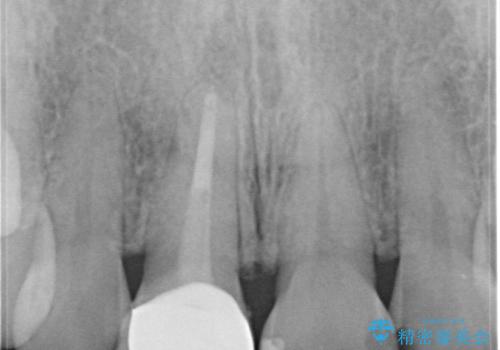

- 「他院で治療した前歯の被せものが一か月の間に2回外れたのでやり変えたい」を主訴に来院されました。

10年前に根管治療を他院で行っており、根尖性歯周炎の予防のため根管治療から行いました。被せものはオールセラミッククラウンで治療を行いました。

10年前にラバーダムシート無しに根管治療を行っており、現在、症状は出ていませんが、根尖性歯周炎の予防のため根管治療から行いました。ホームホワイトニングを2週間行って頂き、その後、オールセラミッククラウンで治療を行っています。

※根尖性歯周炎は根管内の細菌が原因となり発症します。唾液の中には数千億個もの細菌が存在します。したがって、ラバーダムシートを使用し、歯を唾液から守ってあげることが大切になります。当院では、ラバーダムシートの使用に加え、マイクロスコープ(歯科用顕微鏡)、P-MAX(超音波洗浄の機械)を使用して治療を行っています。